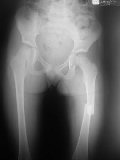

Patologia da Anca

Patologia da Anca Infantil